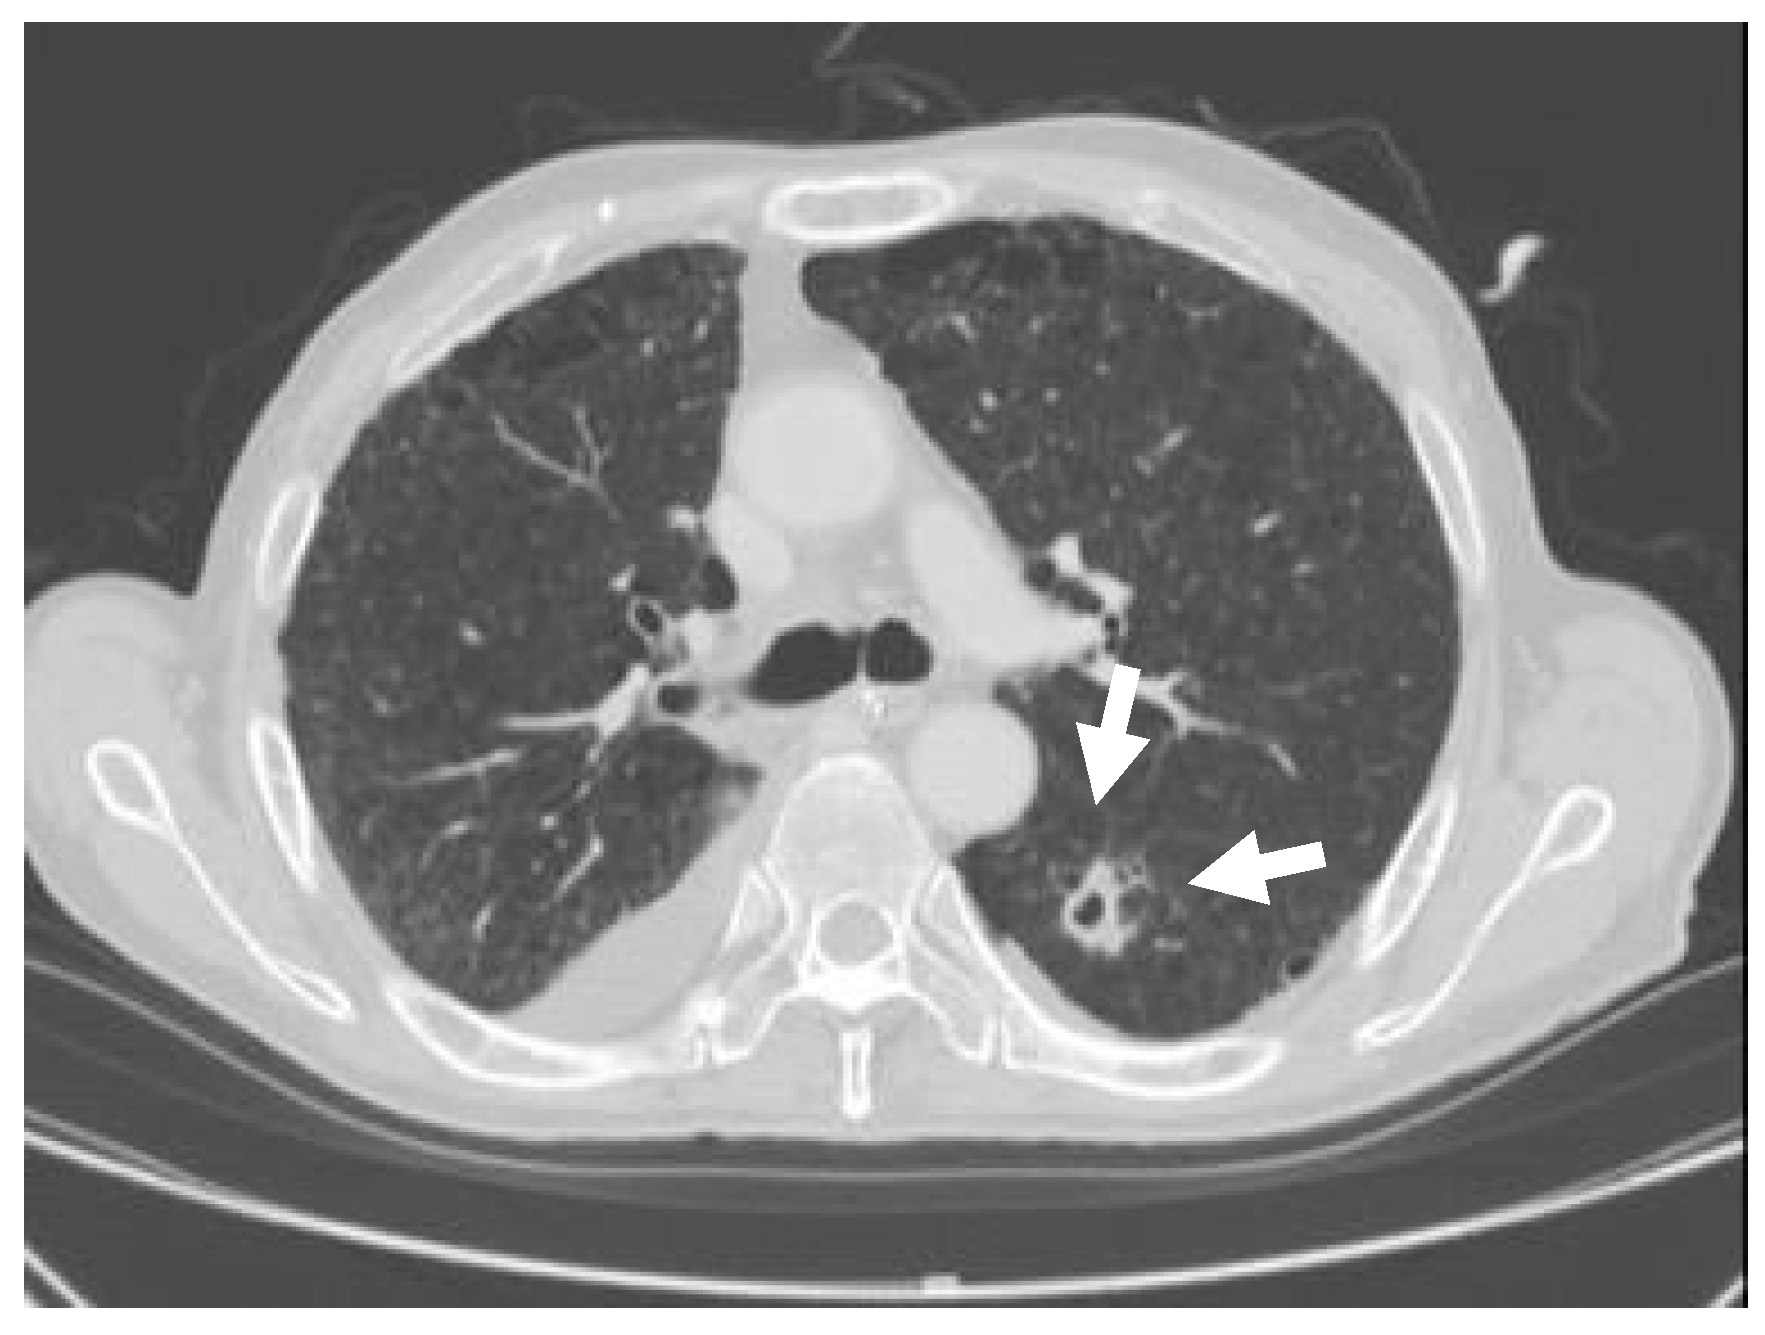

After one month, a 20 mm cavitary nodule appeared in the left lung S6 during the post-operative CT, and a thoracoscopic partial resection of the left inferior lobe was performed while suspecting lung metastasis (Figure 3). The resected specimen was a white solid mass with a charcoal powder deposition, measuring 20 × 15 × 11 mm (Figure 4). The pathology results revealed a pseudo-epithelial granuloma with necrosis and many yeast-shaped fungi with capsules. Encapsulated forms of Cryptococcus were revealed by Groccot staining, and a pathological diagnosis of Cryptococcus infection was made (Figure 5).

Figure 3.

Cavitary nodule. The CT depicted a 20 mm cavitary nodule in the left lung S6.